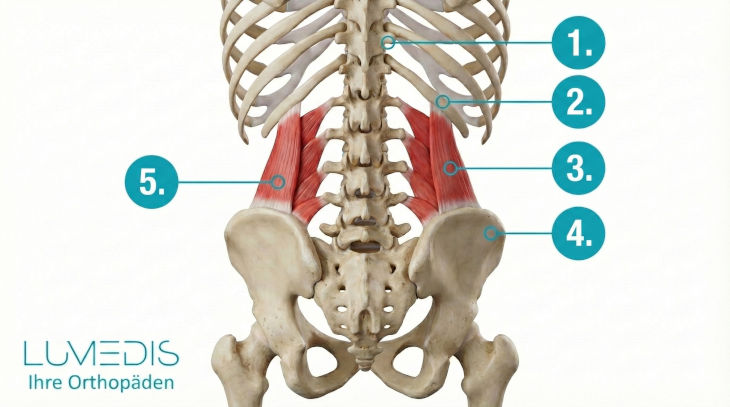

Anatomie der Rückenmuskulatur

Abbildung der Rückenstreckmuskulatur

Musculi multifidii (Teil der autochthonen Muskulatur)

M. quadratus lumborum